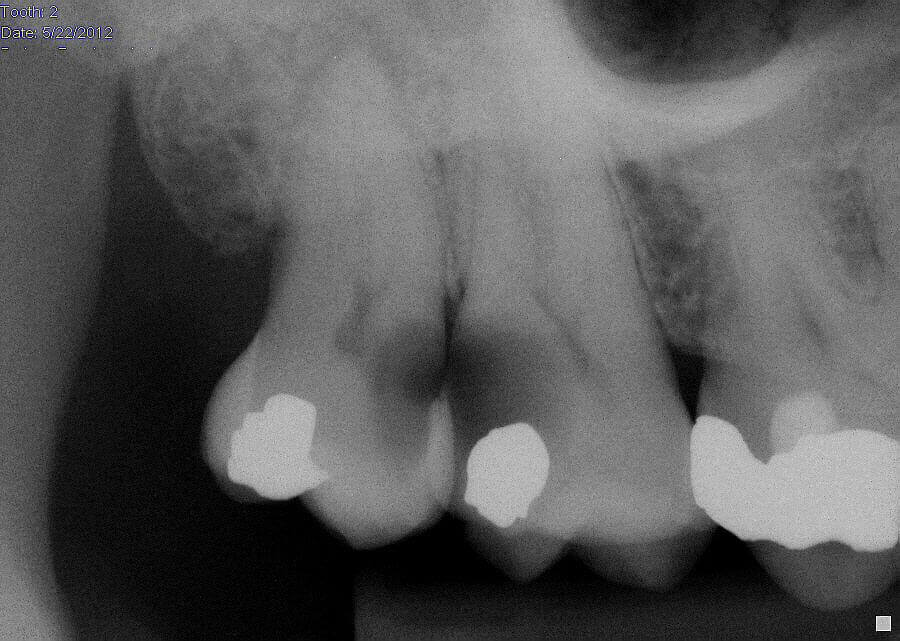

Maxillary Molar with Caries Adjacent to a Third Molar Case Studies Case Study Dental Caries Case reports in dentistry is an open access journal that publishes case reports and case series in all areas of dentistry, including. Caries classification and management in the context of the cariescare international (ccitm) consensus: This study reports a series of successful cases involving the selective removal of carious tissue in permanent molars, with. Fluoride toothpaste, the most readily available. Case Study Dental Caries.